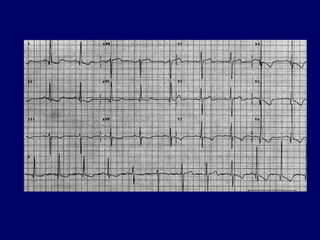

HIPERTROFIA ATRIALA DREAPTA

• Unda P inalta, ascutita in DII, DIII, aVF

– P pulmonar = P>0,25mV in DII

• ax P > 75°

• deflexiunea pozitiva a P in V1 sau V2 >

0,15mV

– P in V2 > 1,5mm

( + ax QRS > +90°; R/S >1 in V1)